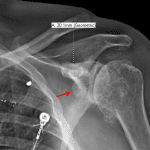

- No acute fracture

- Superior displacement of the clavicle relative to the acromion with widening of the coracoclavicular distance to 30 mm. The distal clavicle tents the overlying skin

- 1.4 cm ossific body projects inferior to the coracoid

- Severe degenerative changes of the glenohumeral joint

- Ballistic fragments overlie the left chest

- Grade V acromioclavicular (AC) separation

No acute fracture.

Superior displacement of the clavicle relative to the acromion with widening of the coracoclavicular distance to 30 mm, consistent with Grade V AC separation. The distal clavicle tents the overlying skin.

1.4 cm ossific body projects inferior to the coracoid, which may represent a loose body in the superior subscapular recess.

Severe degenerative changes of the glenohumeral joint.

Ballistic fragments overlie the left chest.